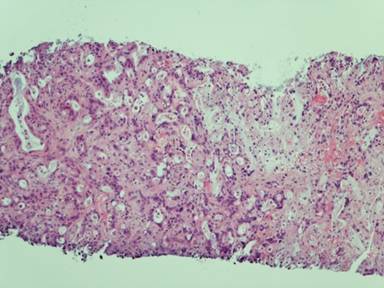

In January 2011 a 69-year-old female patient was admitted to our hospital due to persisting abdominal pain and elevated liver enzymes in the serum. Based on CT-scans (Figures 1 and 2) and laboratory diagnostics, adenocarcinoma of the pancreatic tail with multiple liver metastases was diagnosed. This diagnosis was confirmed histologically by biopsy of one of the liver metastases revealing poorly differentiated adenocarcinoma (Figure 3). Because of the clear constellation of diagnostic findings immunohistochemistry was dispensable. In our interdisciplinary tumor conference palliative chemotherapy was suggested. Because of the patients’ excellent performance status (ECOG 0) a first line therapy including folic acid, fluorouracil, oxaliplatin and irinotecan (FOLFIRINOX) was initiated in February 2011. In follow up staging CT scans showed significant shrinkage of the liver metastases and of the primary tumor, while serum CA 19-9 decreased concomitantly (Figure 4). After 2 years of chemotherapy, in February 2013, liver metastases could hardly be detected anymore, whereas the primary tumor in the pancreatic tail was still detectable and suspicious of residual cancer tissue. Thus, chemotherapy with FOLFIRINOX was continued. Subsequently, the lesion in the pancreatic tail stayed exactly the same size over another year of chemotherapy, while liver metastases did not recur as long as FOLFIRINOX was administered. In April 2014 we additionally performed an FDG-PET-CT-scan to find out whether the primary lesion in the pancreatic tail was still representing vital tumor tissue. Neither in the liver nor in the pancreatic tail FDG-uptake was increased (Figures 5, 6). Thus, we paused chemotherapy for 12 weeks and performed another CT-scan in August 2014 revealing a single metastasis in segment IVb of the liver. This metastasis was treated by radio frequency ablation (RFA). Six weeks later another CT-scan showed no sign of vital tumor tissue in the pancreas or the liver or elsewhere in our patient.

Figure 3. Histology of a liver biopsy (HE; 1:100) done in Feb. 2011. Liver tissue infiltrated a poorly differentiated adenocarcinoma, most probably originating from the pancreatic tail. |